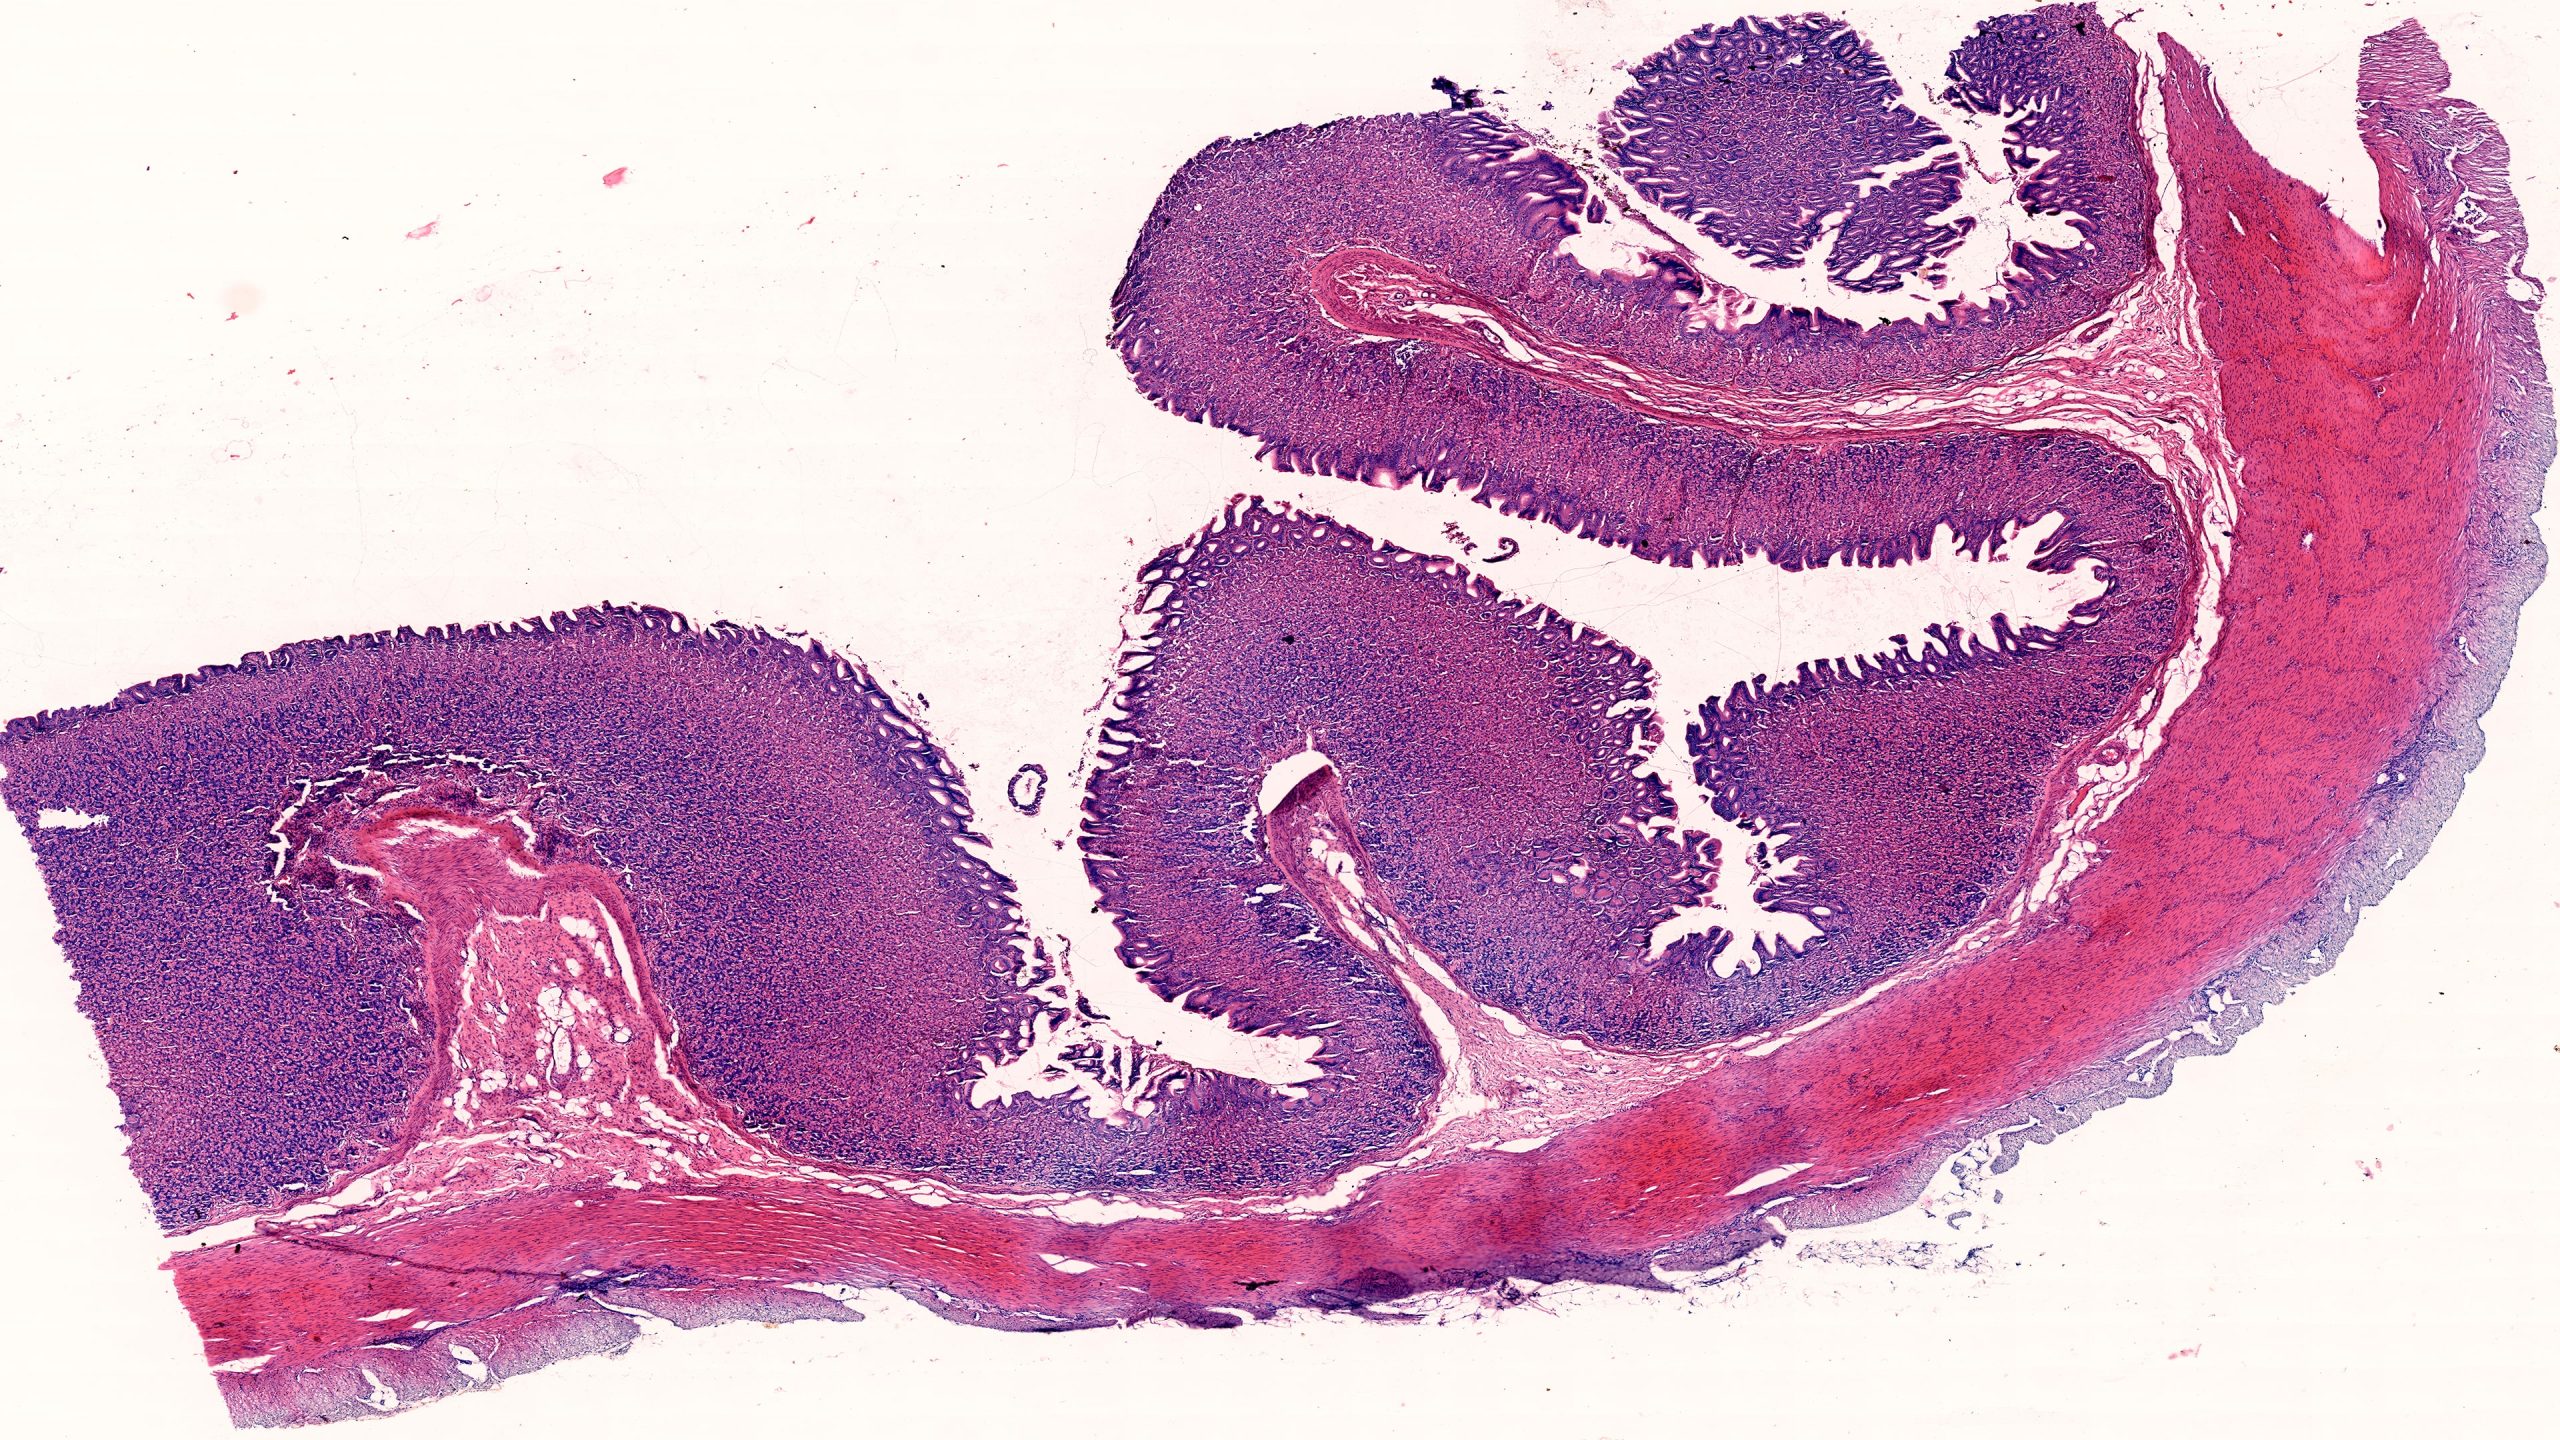

Stomach Pylorus 4X